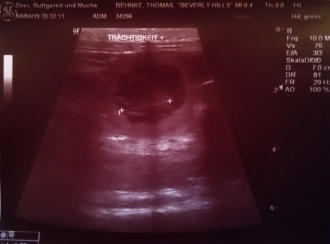

08.04. Ultraschall - Beverly ist trächtig Der Ultraschall hat es bestätigt, was Beverly mit ihrem Verhalten uns schon angedeutet hat. Sie ist trächtig. Wie viele es werden, hat Beverly uns aber noch nicht verraten. Es bleibt weiter spannend.